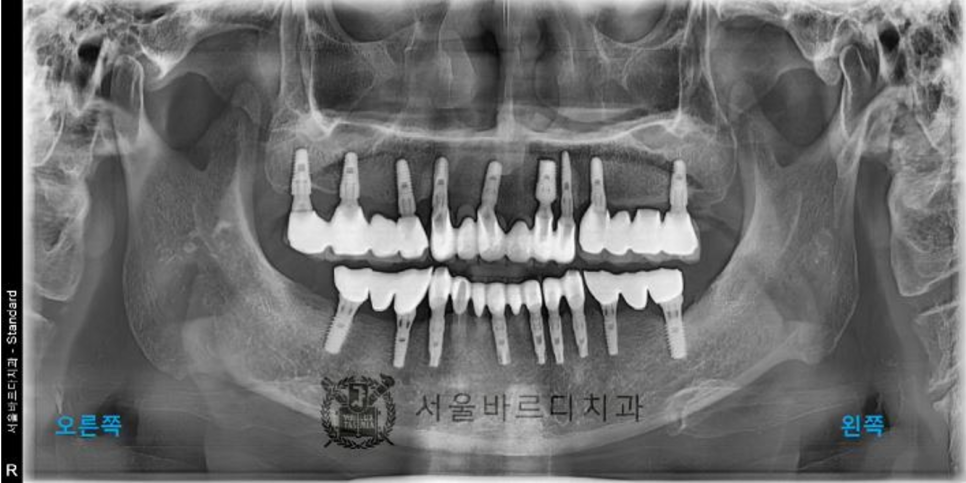

파노라마 엑스레이 촬영 후 검사 결과 전체적으로

잇몸이 많이 내려가신 상태이고

안 좋은 곳들이 많이 있었고,

20년 전에 치료하신 치아들이라 보철물도

여기 저기 많이 깨져있었습니다.

그 중에서 환자분께서는

왼쪽 아래 임플란트 치료를 우선적으로 원하셨습니다

왼쪽 아래 부분의 임플란트 브릿지는 많이 흔들려서

음식을 드실 수 없는 상태이셨습니다.